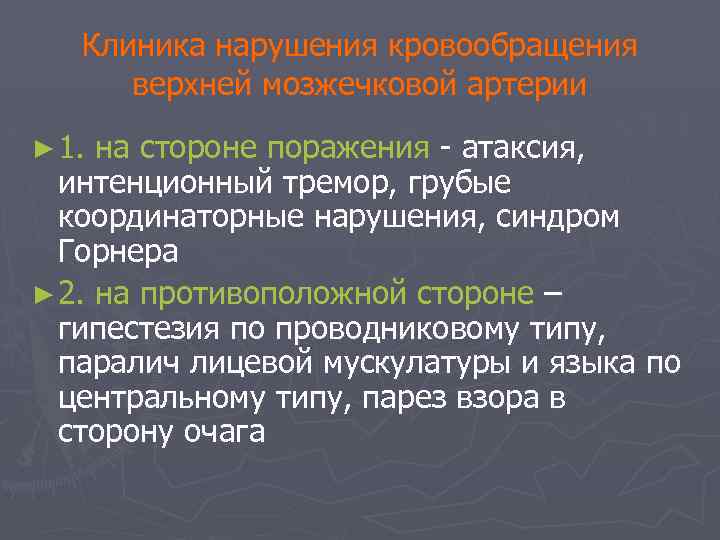

Клиника нарушения кровообращения верхней мозжечковой артерии ► 1. на стороне поражения - атаксия, интенционный тремор, грубые координаторные нарушения, синдром Горнера ► 2. на противоположной стороне – гипестезия по проводниковому типу, паралич лицевой мускулатуры и языка по центральному типу, парез взора в сторону очага